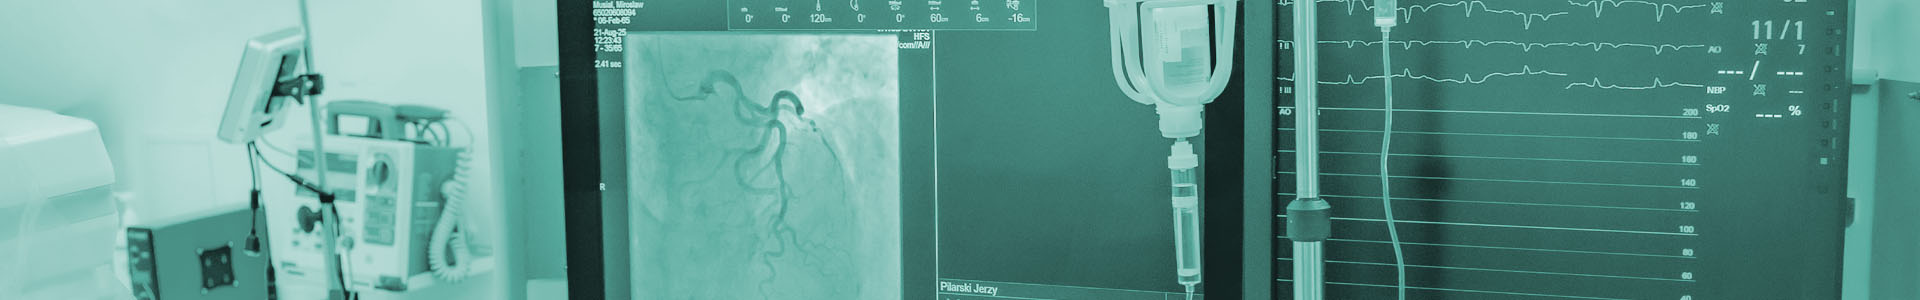

Zakład Hemodynamiki posiadający dwie sale zabiegowe zajmujące się procedurami inwazyjnymi, pracownię elektrofizjologii stosującą nowe metody leczenia zaburzeń rytmu serca i implantację stymulatorów i kardiowerterów oraz pracownię hemodynamiki wykonująca diagnostykę i leczenie choroby wieńcowej.

- diagnostyka i leczenie naczyń wieńcowych (koronarografia, FFR, IVUS, OCT, litotrybsja, rotablacja i angioplastyka naczyń wieńcowych)